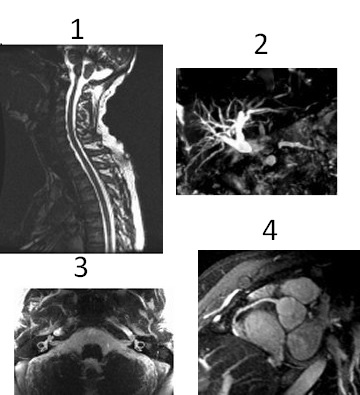

Figure 1. 3D FIESTA images

Table 1. Image legend

NumberDescription

1Cervical spine

2MRCP

3IAC

4Coronary arteries